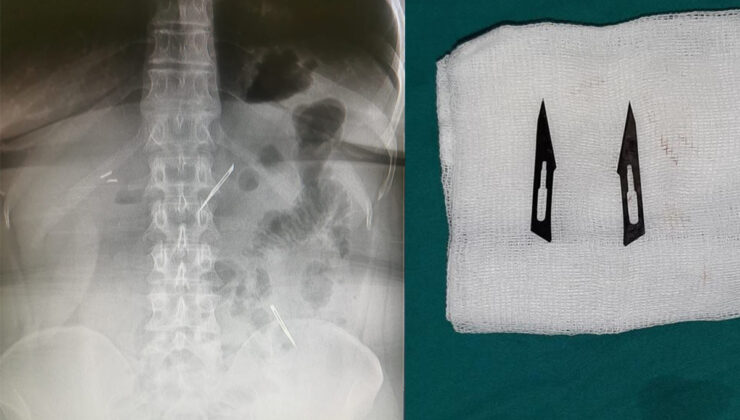

Başkent’te karın ağrısı şikayetiyle hastaneye başvuran 46 yaşındaki kadının midesinde 2 adet neşter tespit edildi. Neşterlerin vücuduna nasıl girdiğini bilmediğini söyleyen kadın, ekmek ile birlikte yutmuş olabileceğini ifade etti. Gerçekleştirilen başarı operasyon ile neşterler vücudundan çıkarılan kadının sağlık durumunun iyi olduğu öğrenildi.

Eğitim ve Araştırma Hastanesi’ne mide ve karın bölgesinde aşırı ağrı şikayeti ile müracaat eden 46 yaşındaki D.E.’nin yapılan tahlil, tetkik ve çeşitli görüntülemelerden sonra bağırsak kısmında 2 adet neşter olduğu tespit edildi. Genel cerrahi kliniği tarafından zorlu bir ameliyat sonrasında neşterler kadının vücudundan çıkarıldı.

46 yaşındaki D.E. neşterleri nasıl yuttuğunu bilmediğini tahminen ekmek ile birlikte yutabilmiş olabileceğini ifade etti. Ameliyatı gerçekleştiren Sağlık Bilimleri Üniversitesi Ankara Atatürk Sanatoryum Eğitim ve Araştırma Hastanesi Genel Cerrahi Kliniği Eğitim ve İdari sorumlusu Prof. Dr. Hakan Buluş ise hastanın yoğun şikayetleri üzerine çektikleri röntgen sonrasında 2 adet neşteri görünce şaşkına uğradıklarını söyledi.

“2 adet yabancı cismin bistüri (neşter) ile uyumlu olduğunu gördük”

Hastanın şikayetlerinin artması üzerine gerçekleştirilen tetkiklerde 46 yaşındaki kadının karın bölgesinde 2 adet yabancı cisim olduğunu tespit ettiklerini, detaylı inceleme sonucunda bu cisimlerin neşter olduğunu fark ettiklerini belirten Prof. Dr. Buluş, “Yaklaşık 10 gün önce kliniğimize karın ağrısı ve bulantı şikayetleri ile başvurdu. Bizim yaptığımız fiziki muayene ve tetkiklerinde hastanın direkt karın grafisinde 2 adet yabancı cisim olduğunu tespit ettik. Aslında yabancı cisim bizim güncel grafiğimizde sık karşılaştığımız bir durum değil, fakat nadir de olsa görebildiğimiz bir patoloji. Biz de bunun üzerine ayrıntılı değerlendirmeler ve tetkikler yaptık. Sonrasında 2 adet yabancı cismin bistüri (neşter) ile uyumlu olduğunu gördük. Bunun üzerine hastanın şikayetlerinin de artması üzerine, ameliyat kararı verdik. Yaptığımız ameliyatta ince bağırsağın yaklaşık 180’inci santimetresinde bu yabancı cisimlerin olduğunu tespit ettik. Bunun üzerine ameliyatla bunları çıkarttık. Hastamızın sağlık durumu şuan gayet iyi. Ameliyattan sonraki üçüncü günü. Şuan bir problemi yok, inşallah birkaç gün içerisinde şifa ile taburcu etmeyi düşünüyoruz” şeklinde konuştu.

“Çıkardığımız yabancı cisimler bizim ameliyatlarda sıkça kullandığımız 11 numara dediğimiz bir bistüri tipi”

Çıkardıkları cismin, neşterin normalde ameliyatlarda kullanılan bir malzeme olduğunu söyleyen Prof. Dr. Buluş, “Çıkardığımız yabancı cisimler bizim ameliyatlarda sıkça kullandığımız 11 numara dediğimiz bir bistüri tipi. Ebatları da yaklaşık 4 santime yarım santim ebatlarında. Ucunun sivri olması nedeniyle ince bağırsak mukozasına saplanarak enflamasyon ve bir karın ağrısı yapması, sonrasında da ağrı şikayetlerinin artmasına neden olmasından dolayı ameliyat kararı verdik” diye konuştu.